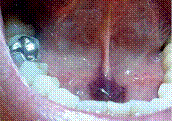

En una muestra de pacientes positivos a la COVID-19 fueron halladas múltiples lesiones ulcerativas de color naranja y amarillentas puntiformes con halo eritematoso y distribución simétrica en el paladar duro, lesiones ampollares en labio; gingivitis descamativa, úlceras y ampollas compatibles con estomatitis herpética recurrente en la mucosa palatina, así como sensación de quemazón y dolor de la orofaringe; lesión ulcerativa de patrón irregular al dorso de la lengua y presencia de petequias milimétricas sin eritema en paladar duro y blando, lo cual sugiere que están relacionadas con la manifestación clínica de esta cepa del virus (figura 1 y figura 2).16,17,18

Acerca de la afección conocida como lengua COVID, especialistas 22 indican, que la lengua por coronavirus posee características singulares con lesiones a nivel de la boca, la lengua ancha, eritematosa, sin las papilas gustativas. Esta afección de lengua y mucosa de la boca da sensación de prurito y ardor en la lengua. Las manifestaciones bucales se pueden presentar entre 4 días antes del inicio de los síntomas respiratorios y hasta 12 semanas después del inicio de los síntomas. No es muy específico, pero se observó que es más frecuente en relación con la disminución del olfato y del gusto (figura 3).

De igual manera, se han encontrado otras alteraciones en la lengua, la más frecuente fue la papilitis lingual transitoria anterior en forma de U asociada o edema lingual; estomatitis aftosa, mucositis, glositis con depapilación en parches, es decir, zonas de la lengua más lisas y que se asocian en muchas ocasiones a la pérdida del gusto (figura 4). Este síntoma puede ser signo de COVID-19, unido a los ya descritos como fiebre o tos, y puede facilitar la detección precoz de la infección; boca urente, lengua saburral y enantema en menor porcentaje de los casos.23